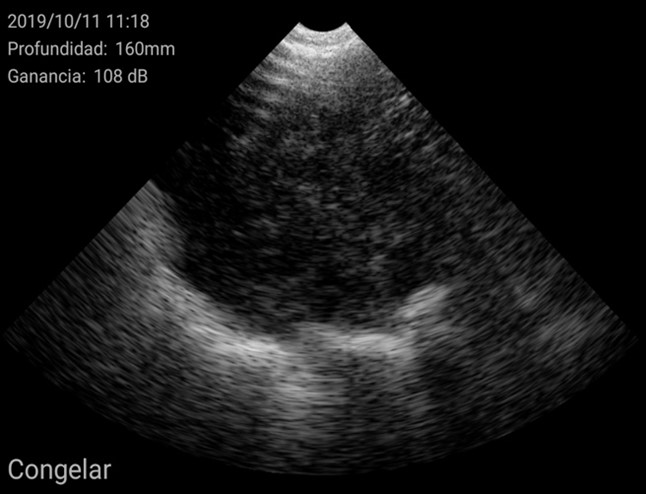

El diagnóstico se basó en la determinación del tamaño del útero y su posición en relación con otras estructuras como la vejiga urinaria o las asas intestinales. En general, se encuentra en posición ventral a la vejiga. Cuando el tamaño del útero es pequeño, ocupa muy poco espacio en la pantalla, de esta manera se considera una hembra impúber.

Imágenes de cerdas impúberes con el ecógrafo W3 de Kubus